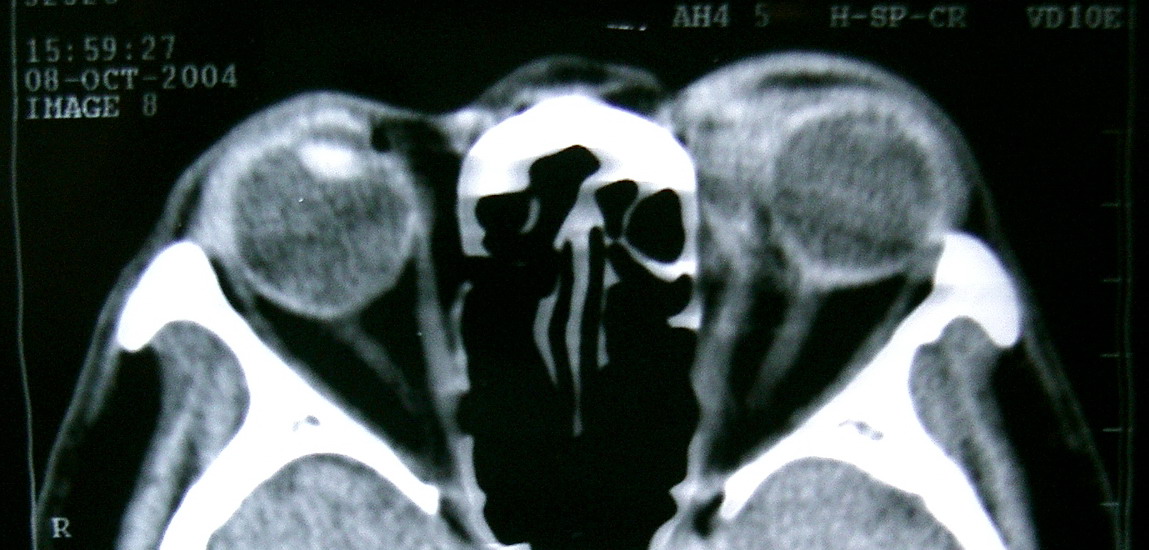

2,上眼眶CT示:左眼眶内肿物

此主题相关图片如下:

按此在新窗口浏览图片

眼眶冠扫,平扫CT:

左眼球内上方可见不规则软组织块影,大小约2.5*1.0CM,与邻近组织分界不清,相邻之内直肌、上直肌增粗,眼环正常,眶壁骨质无破坏,左上颌窦底部可见粘膜增厚,其余副鼻窦未见异常。

IMP:1,左眼眶肿物;2,左上颌窦炎